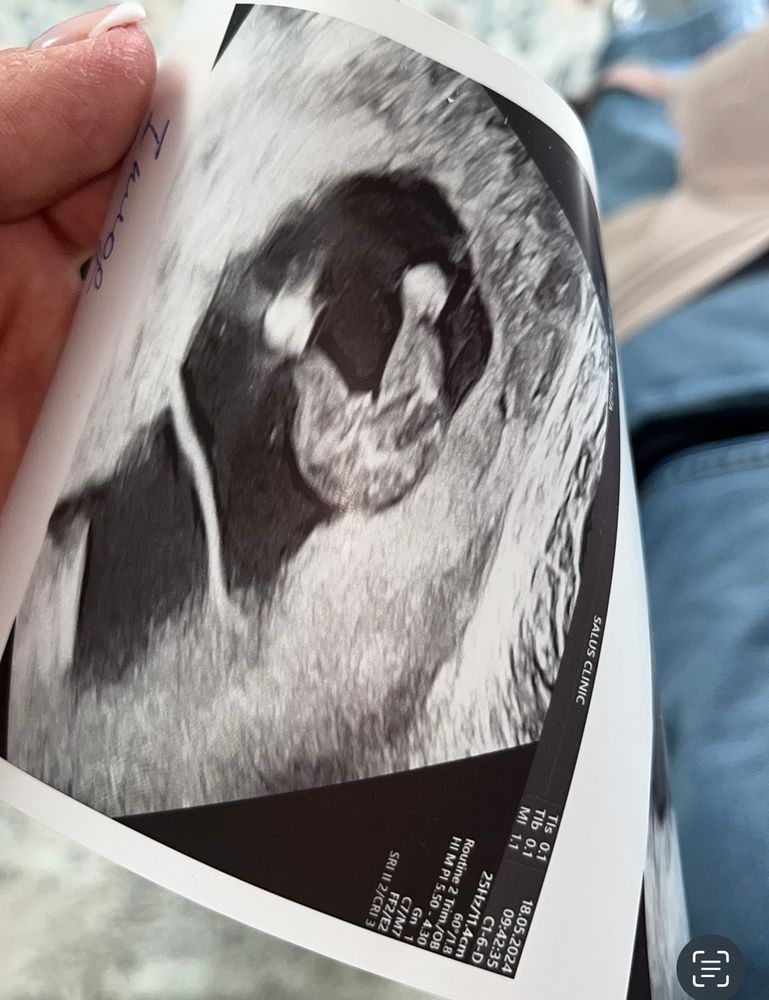

Ксения Пантелейчук, у сына в 15 недель было вот так ) Изображение

13.06.2024